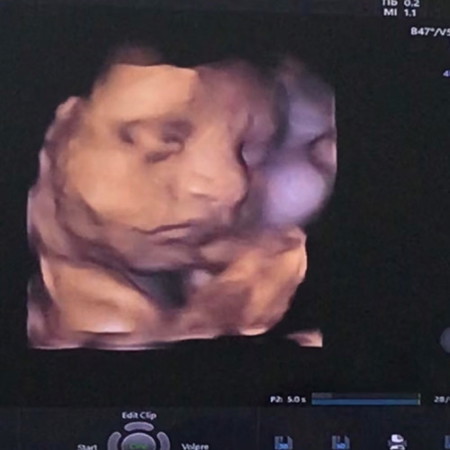

นับวันรอเจ้าตัวเล็ก ยังคงตื่นเต้นเหมือนเดิมเลย คุณลุงหมอบอกว่าน้ำหนักน้องตามเกณฑ์แต่เกือบเกินเกณฑ์ไปเหมือนกัน แม่ทานทุกอย่างลงตัวเล็กหมดเลย ออกมาคงบันเทิงหน้าดู 33Week รอบนี้ไม่ปิดหน้า เปิดหน้าให้แม่เห็นได้ชื่นใจ ❤️ #ทีมลูกคนที่2 #ทีมลูกสาว #คลอดธรรมชาติ #กำหนดคลอด17/66 (ขอดูภาพอัลตร้าซาวของตัวเล็กแต่ละบ้านหน่อยค่ะ)